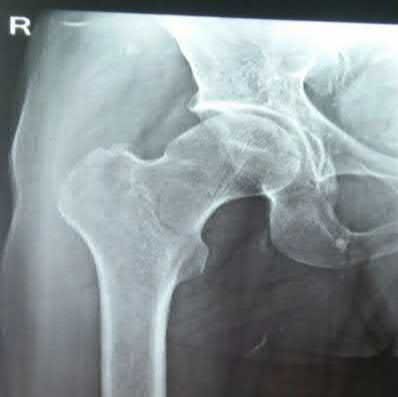

A 12-year-old obese boy presents with vague left thigh and knee pain. He is diagnosed with a Slipped Capital Femoral Epiphysis (SCFE) as seen in similar clinical scenarios.

During percutaneous in-situ fixation, unrecognized penetration of the guide wire into the hip joint occurs. What is the most likely specific complication resulting from this technical error?

Explanation

Chondrolysis is a severe complication of SCFE characterized by rapid destruction of the articular cartilage. While it can occur idiopathically, its most established iatrogenic cause is unrecognized intra-articular hardware penetration. The 'approach-withdraw' fluoroscopic technique is required during pinning to assure pins are entirely intraosseous. Avascular necrosis (AVN) is usually due to damage to the epiphyseal blood supply (retinacular vessels) secondary to the initial displacement, forceful closed reduction, or posterosuperior pin placement.